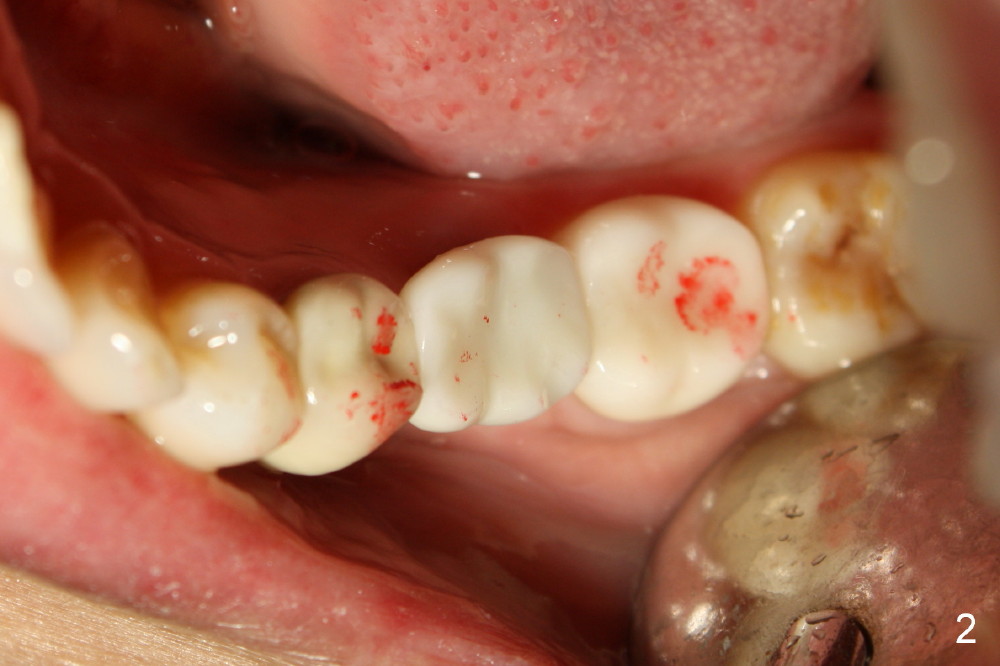

Fig.1 shows a model of #18 and 19 crown prep. #18 is a natural tooth, whereas #19 is an implant. In order to have less trauma from occlusion, the occlusal table should be narrow buccolingually for the implant crown (as shown in Fig.2). The occlusal contact should be lighter than that of the neighboring teeth as well.

This type of adjustment should be preferably done in laboratory.